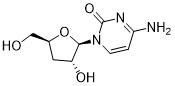

馬鞍山致研生物醫(yī)藥科技有限公司成立于馬鞍山市鄭浦港新區(qū)現(xiàn)代產(chǎn)業(yè)園。公司專(zhuān)注于生物小分子、醫(yī)藥中間體相關(guān)產(chǎn)品的研發(fā)和生產(chǎn),產(chǎn)品主要包括DNA亞磷酰胺單體、RNA亞磷酰胺單體、特殊單體以及按照客戶(hù)要求定制的RNA和DNA,并且公司提供定制合成等方面的研究服...

馬鞍山致研生物醫(yī)藥科技有限公司成立于馬鞍山市鄭浦港新區(qū)現(xiàn)代產(chǎn)業(yè)園。公司專(zhuān)注于生物小分子、醫(yī)藥中間體相關(guān)產(chǎn)品的研發(fā)和生產(chǎn),產(chǎn)品主要包括DNA亞磷酰胺單體、RNA亞磷酰胺單體、特殊單體以及按照客戶(hù)要求定制的RNA和DNA,并且公司提供定制合成等方面的研究服...